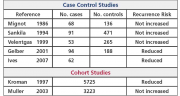

| 16:37, 7 במרץ 2015 | Gold table3.jpg (קובץ) |  |

233 קילו־בייטים | Motyk | 1 | |

| 16:35, 7 במרץ 2015 | Gold table2.jpg (קובץ) |  |

210 קילו־בייטים | Motyk | 1 | |

| 16:32, 7 במרץ 2015 | Gold table1.jpg (קובץ) |  |

373 קילו־בייטים | Motyk | 1 | |